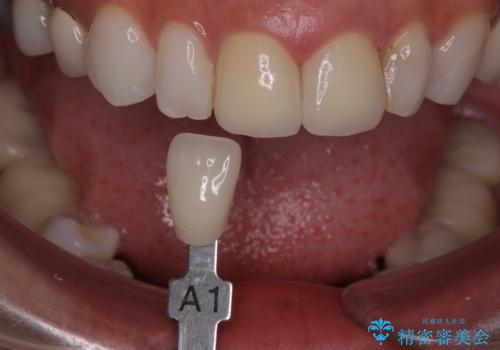

ラミネートベニヤの破折 ジルコニアクラウンによるやり替え

- 欠けてしまった前歯のラミネートベニヤと見た目の改善を求めて来院されました。

歯の大きさの不揃いと、虫歯の再発を認めたためラミネートのやりかえではなく一挙に問題の解決のできるジルコニアクラウンでの治療を計画します。